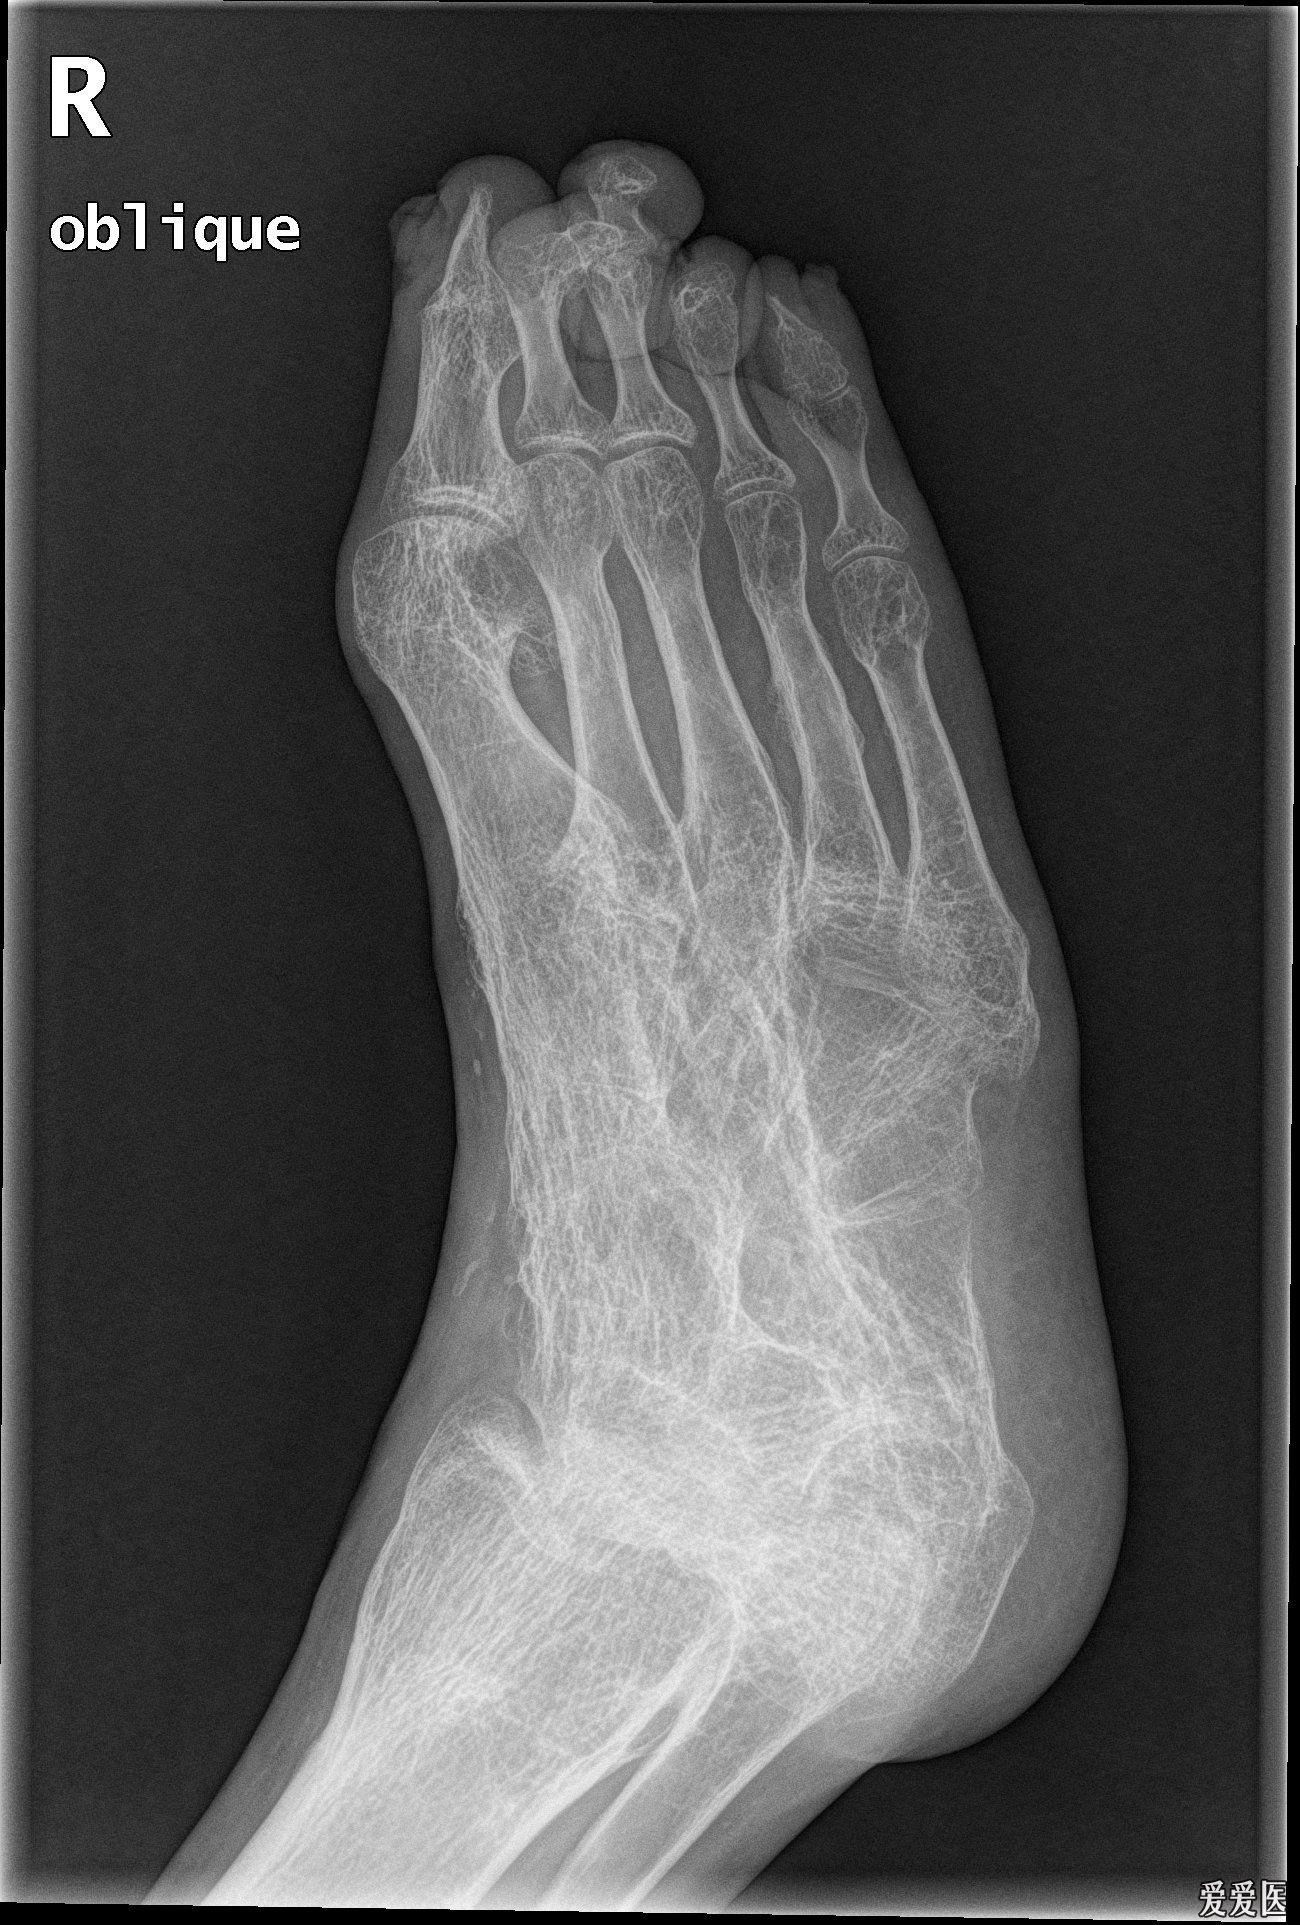

请教各位10765右足正斜位片